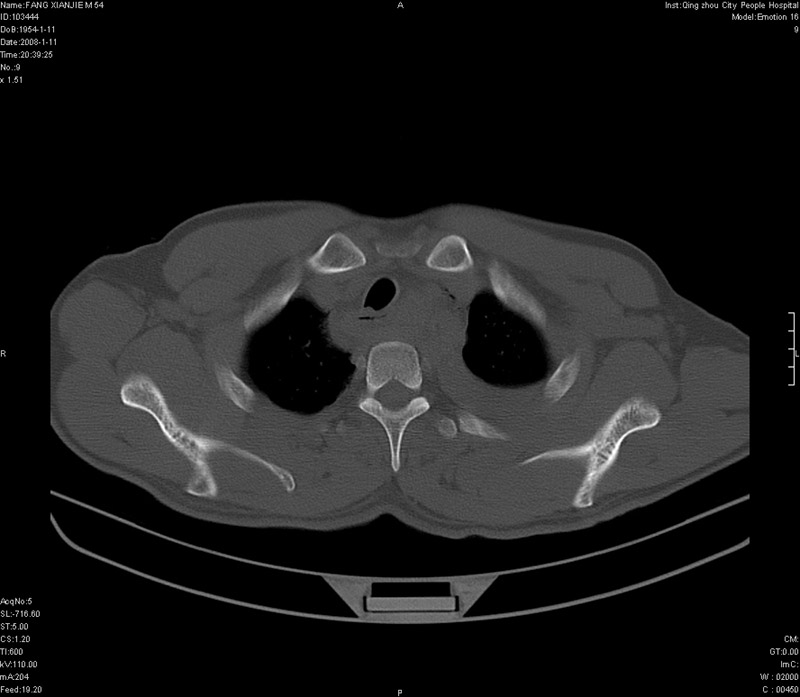

男性,40岁。胸部被车压伤伴胸痛1小时来院就诊。检查:一般情况尚可,血压110/80,胸部及上腹部压痛。结果在三天后公布。骨窗在横断位、冠矢状显示肋骨、胸椎、和胸骨未见骨折征象。

ct11308:胸部外伤1小时(证实病例) (2008-1-13 16:2)结果如下:病人入院后两小时后症状加重,8小时后在征得病人家属同意做了ct增强扫描。如下图。最终临床诊断:外伤性胸主动脉破裂并纵隔内血肿。由于有运动性伪影,胸骨在矢状面重建的图像似有骨折征,这是一种假象,我们称之为“假骨折”,这在多层ct重建中经常性遇到,必要时要结合横断图像鉴别之。现在,病人的一般情况较差,是否要手术家属尚有争议,如果手术修补,难度较大,需要专门预定制作固定支架。

以下是引用拾荒者在2008-1-16 18:46:00的发言:[br]ct11308:胸部外伤1小时(证实病例) (2008-1-13 16:2)结果如下:病人入院后两小时后症状加重,8小时后在征得病人家属同意做了ct增强扫描。如下图。最终临床诊断:外伤性胸主动脉破裂并纵隔内血肿。由于有运动性伪影,胸骨在矢状面重建的图像似有骨折征,这是一种假象,我们称之为“假骨折”,还有双侧肋骨的“假骨折”,这在多层ct重建中经常性遇到,必要时要结合横断图像鉴别之。现在,病人的一般情况较差,是否要手术家属尚有争议,如果手术修补,难度较大,需要专门预定制作固定支架。[br][br]再次表示感谢!